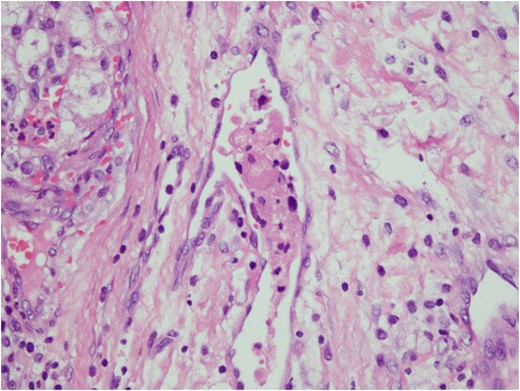

Histologic sections of the mass show distinct variably sized and shaped collections of uniform polygonal tumor cells, separated by fibrovascular septa and delicate capillary-sized vascular channels lined by flattened endothelium at low magnification (Fig. 5). Within the tumor nests, there is loss of cellular cohesion and necrosis of the centrally located cells in the nests results in the pseudo-alveolar pattern (Fig. 6). Vascular invasion is also present (Fig. 7). The individual tumor cells have distinct cell borders and abundant eosinophilic to clear, somewhat granular cytoplasm surrounding a central nucleus with variably sized nucleolus. Nuclear atypia is rarely seen. Mitotic figures are uncommon. The cells contain rhomboid or rod-shaped crystalline inclusions that are faintly apparent on routine histology and are better demonstrated with periodic acid-Schiff stain after diastase digestion (Fig. 8).

Tumor cells are arranged in organoid or nesting pattern. The nests are vary in size and shape and are separated by delicate thin fibrous septa containing vascular channels.